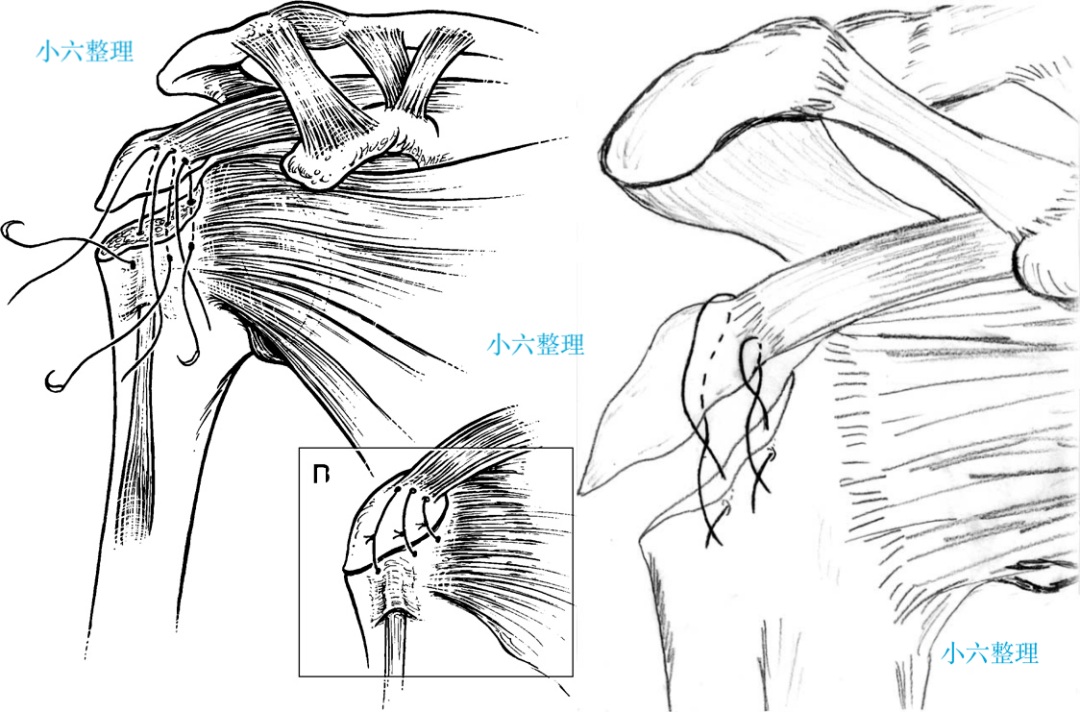

肱骨大结节骨折 ORIF,术前 X 线片显示肱骨大结节骨折情况;术中暴露肱

肱骨大结节骨折 ORIF,术前 X 线片显示肱骨大结节骨折情况;术中暴露肱